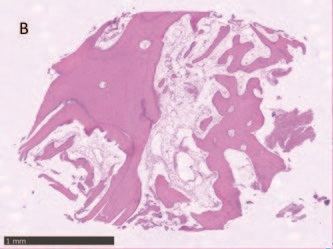

Гистологический анализ показал хорошо организованную, в основном зрелую ткань, образованную компактной пластинчатой костью с четко очерченными костными пластинками вокруг каналов Гаверсияна и Фолькмана, окруженных меньшими участками, в которых пластинки были менее организованными и богатыми остеоцитами на стадии созревания. Количество минеральной матрицы - от 69% до 72% - было особенно значительным. Воспалительного инфильтрата не наблюдалось.

Рис. 9 – Фрагмент В образца кости, взятый в 4,5, показывает широкие участки зрелой костной ткани и медуллярного компонента.

Рис. 10 – Как видно, в некоторых медуллярных областях происходит отложение нового костного матрикса (синяя стрелка). Кость в пластинчатой форме свидетельствует о развитом состоянии созревания ткани.

Рис. 11 – Голубая область определяет участок с вероятным присутствием носителей, предполагает, что новая кость могла быть отложена именно из места трансплантации.

Рис. 12 – Гистоморфометрическое исследование. Минерализованный костный матрикс занимает примерно 70% образца. Остаточный биоматериал составляет менее 2%.